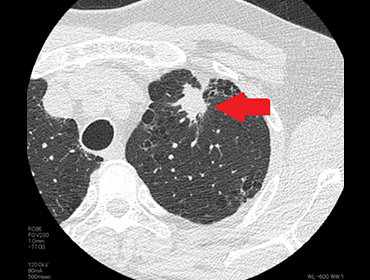

胸部CTを用いた肺ガン検診について | 市立秋田総合病院,胸部CTのおすすめ|日本赤十字社 熊本健康管理センター,レジデントノート増刊:読影力がグッと上がる!胸部X線写真・CTの読み方、考え方〜疾患別に読影の基本と各科での経過観察のポイント、撮影のタイミングがイチからわかる! - 羊土社,胸部CT2(縦隔条件),胸部CTの適応と基本的読影2: やさしイイ呼吸器教室